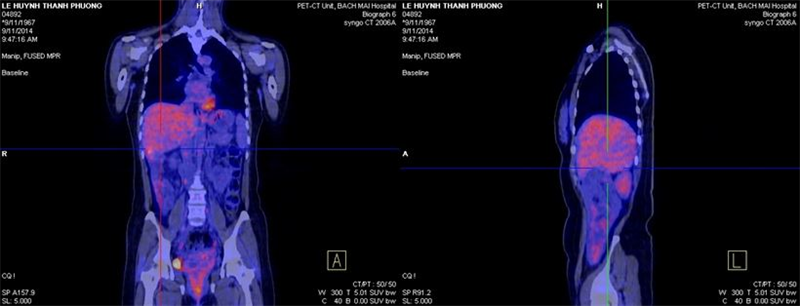

Bệnh nhân được chụp PET/CT đánh giá, (ngày 9/11/14) kết quả cho thấy: Gan: Hạ phân thùy VI có vùng tăng tỷ trọng trên hình ảnh cắt lớp vi tính nhưng không tăng hấp thu F-18 FDG, kích thước 1,8x 2,1cm. Ngoài ra không thấy bất thường khác.

Hình 4,5,6: Kết quả PET/CT sau điều trị (vòng tròn đỏ chỉ tổn thương): khối tổn thương di căn tại gan trái đã thu nhỏ kích thước hơn trước